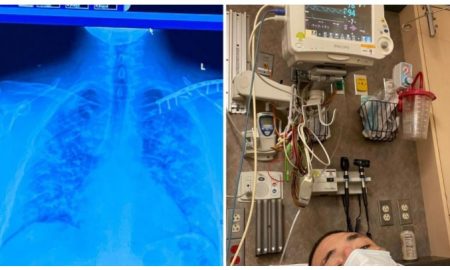

37.0KOstali sportoviFOTO Legendarni UFC borac zaprepastio snimkom: Pogledajte mu pluća nakon korone

On je još ranije otkrio da se nije vakcinisao...